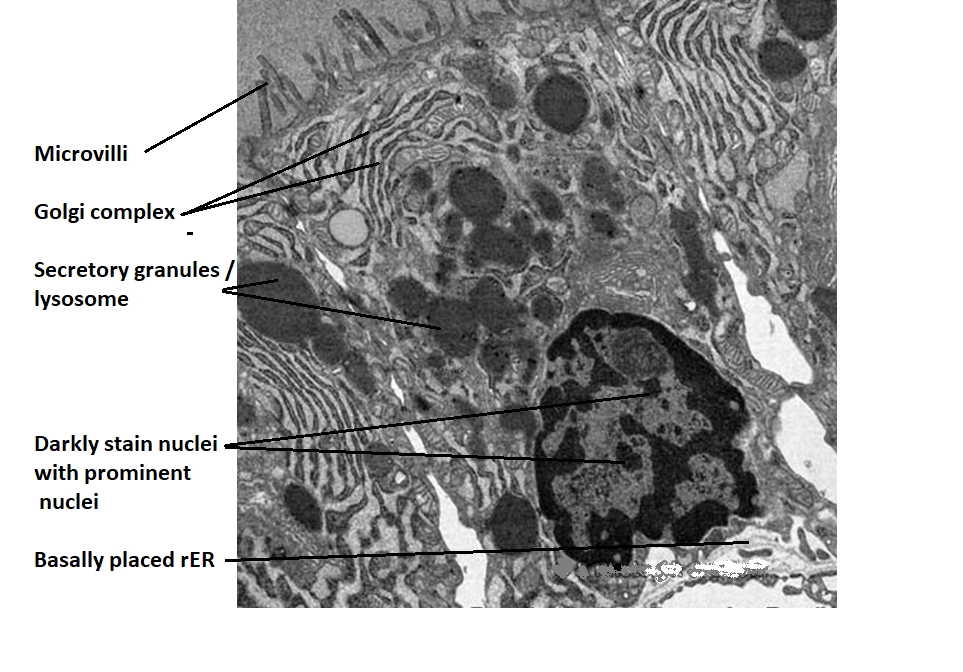

Nuclei

It contains comparatively dark nuclei with two or three

prominent nucleoli

Golgi complex

Golgi complex are supranuclear in position

Secretory vesicles

Few and Present in apical region

rER

Present basally

Lysosome

Abundant

Microvilli

Present